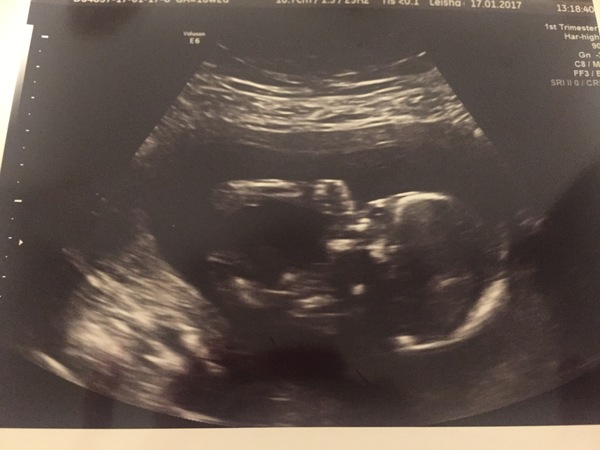

Sounds promising mouse. I had my 16 week midwife appt this morning. All was fine, they listened to the heartbeat - took ages to find it so I was glad I'd had the scan on Tuesday as I was much calmer than I would have been! I've attached a picture of my scan, the baby is sucking it's thumb which I love.

Great scan seahawk! Pleased all was fine this morning.

That is an amazing scan pic seahawk!

Thanks everyone, I was so happy to get a good pic, the other scan pics were just a blur!